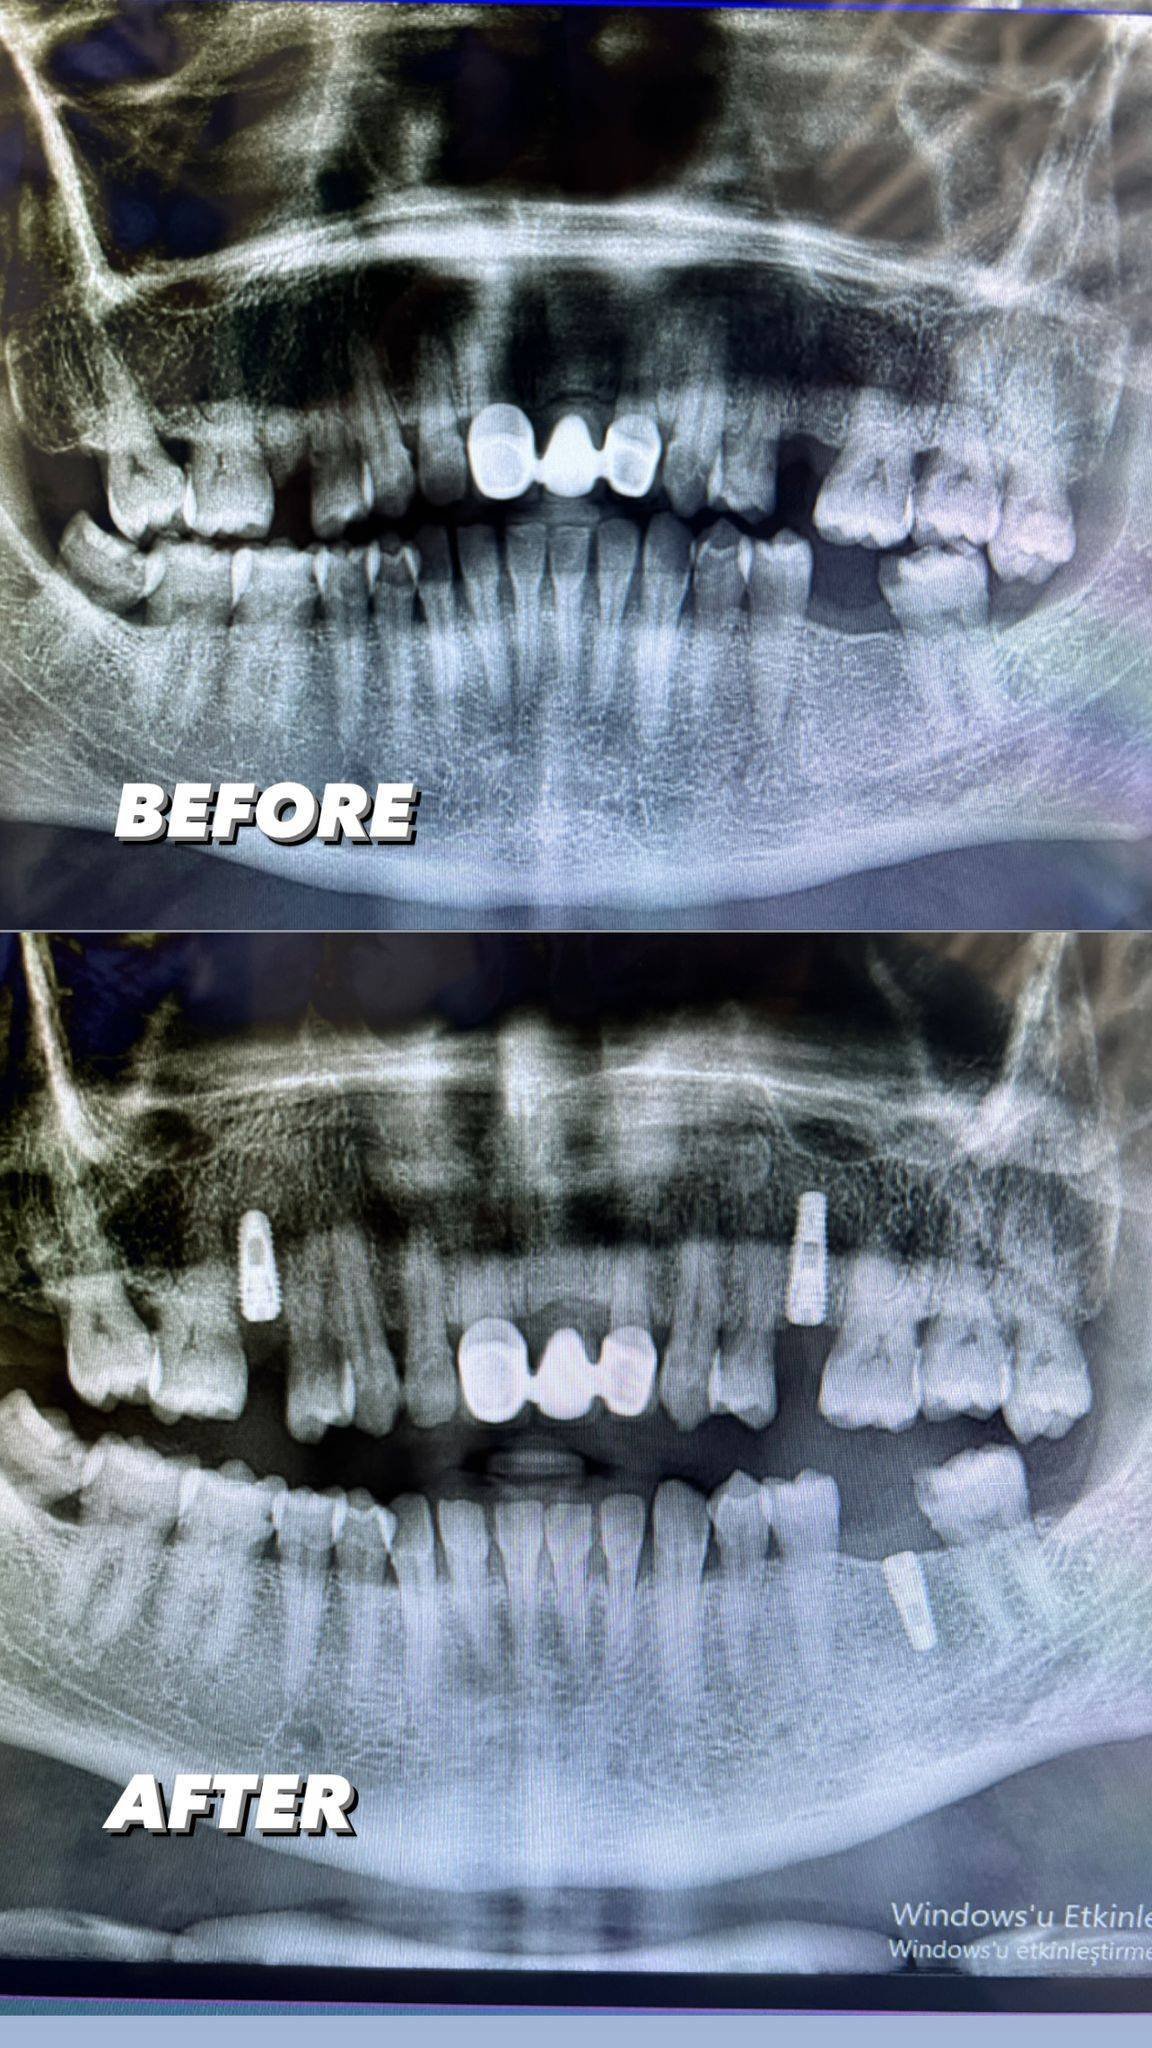

Ağızda eksik olan diş veya dişleri tamamlamak için çeneye yerleştirilen vida ya da vidalar yardımıyla yapılan tedavidir. Eksik olan dişler bu vidaların üzerine yerleştirilmektedir. Tek bir diş için uygulanabileceği gibi uzun diş boşluklarında da bu tedavi yöntemi kullanılabilmektedir. Kişinin kemik yapısının sağlamlığı ve diş eti sağlığı tedavide başarıyı artırmaktadır.

implant tedavisi uygulandıktan sonra normal bekleme 3 ay olan ve bu süre zarfı sonunda üzerine eklenen zirkonyum kaplamayı. Bekleme sürecini 3 aydan , 72 saat’e başarılı bir şekilde düşürüyoruz.